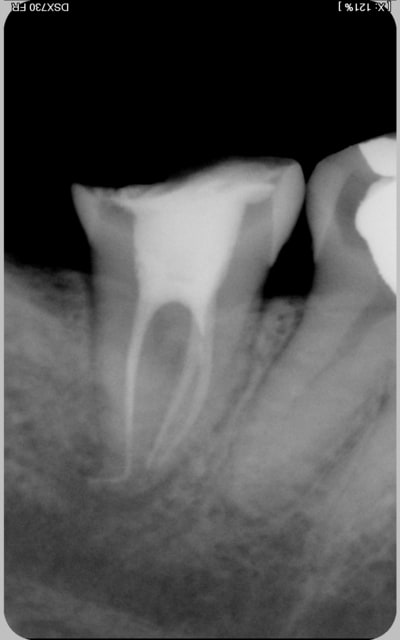

encore des radios,peut-etre assez moyen comme traitement...mais je vu pire...

les dernieres radios. patient en urgence ,abces... il voulait pas extraire la dent. j'ai lui bien explque et il a choisi de essayer de garder la dent. retrait,pas d'isolation avec la digue donc pas de tenon fibree,amalgam et screw post.traitement fait il ya 2 ans je crois.patient fidel de cabinet maintenent.

j'ai jamais utilise en roumanie l'amalgam et ca s'utilise pas du tout dans le cabinet du roumanie.